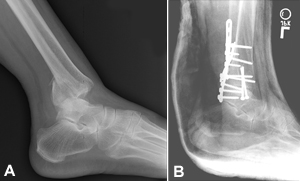

(Left) X-ray of a medial malleolus fracture. (Right) Surgical repair of a medial malleolus fracture with a plate and screws.

If the fracture is out of place or the ankle is unstable, surgery may be recommended.